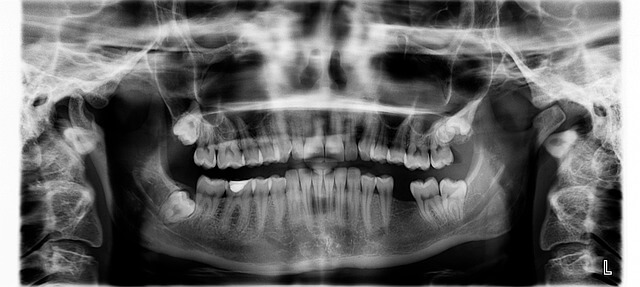

풍치는 잇몸 질환의 일종으로, 세균이 잇몸 속에 쌓이면서 염증을 일으키는 병이에요. 풍치의 가장 초기 증상은 아주 미세하게 잇몸이 붓거나 양치 중 피가 나는 정도로 시작됩니다. 하지만 이러한 변화를 간과하면 점점 잇몸 뼈가 손상되고 치아가 흔들릴 수도 있습니다. 저 역시 처음엔 단순한 잇몸 피로로 착각했지만, 시간이 지나면서 잇몸이 들뜨고 음식물이 자주 끼더군요.

초기 풍치의 대표적인 징후는 다음과 같습니다. - 잇몸 붓기와 미세한 통증 - 양치 후 피가 자주 남 - 입 냄새의 증가 - 특정 치아 주변의 시림 현상 이런 증상이 있다면 이미 염증이 진행 중일 가능성이 높습니다.